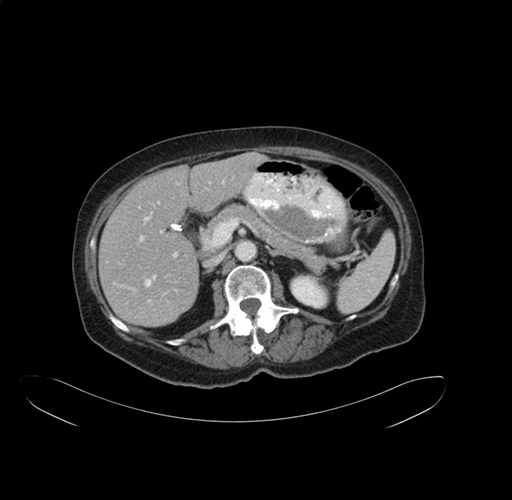

Pre-Chemo: Axial Venous

Axial Venous